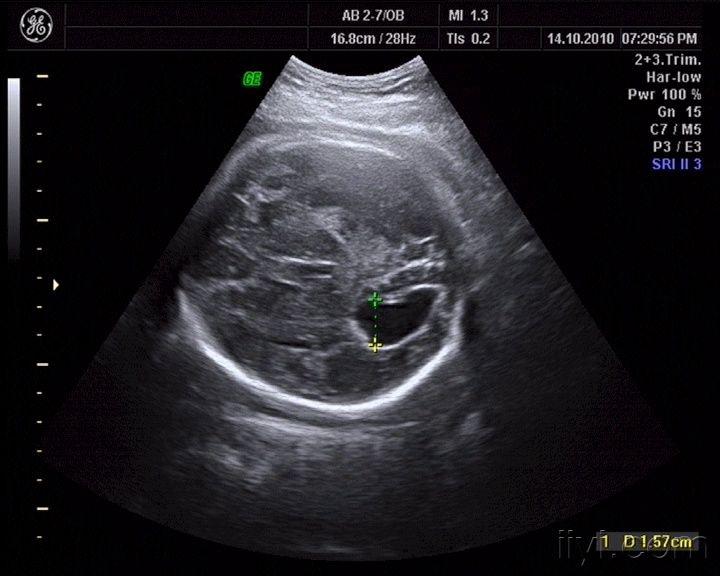

胎儿脑室见一液深20mm无回声暗区

图片尺寸2304x1704